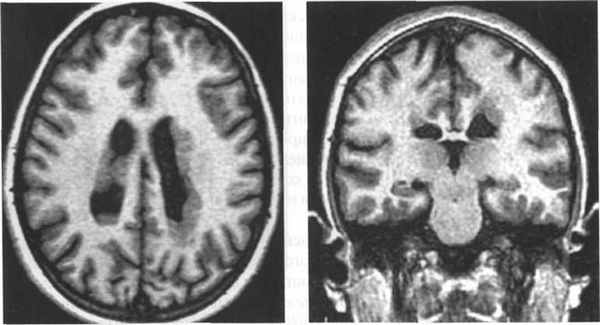

Кроме того, была проведена магнитно-резонансная томография головного мозга (аппарат Hitachi Airis Mate 0,2 Тесла), согласно которой на аксиальных срезах определялись билатеральные лентовидные зоны, соответствующие серому веществу головного мозга, расположенные преимущественно субкортикально. Изгибы гетеротопированных слоев повторяли основную складчатость кортикальной поверхности. На коронарных срезах подтверждалось субкортикальное расположение гетеротопированных зон. В коре видимых диспластических изменений не отмечено. Таким образом, можно утверждать о наличии у пациентки МР-признаков билатеральной ламинарной гетеротопии серого вещества, что характерно для синдрома «двойной коры» (рис. 2).

Рис. 3.21. Лентовидная гетеротопия. МРТ.

а - IR ИП, аксиальная плоскость; б - Т2-ВИ, аксиальная плоскость.

Полоса гетеротопированного серого вещества отделена

слоем белого вещества от коры и желудочков мозга.